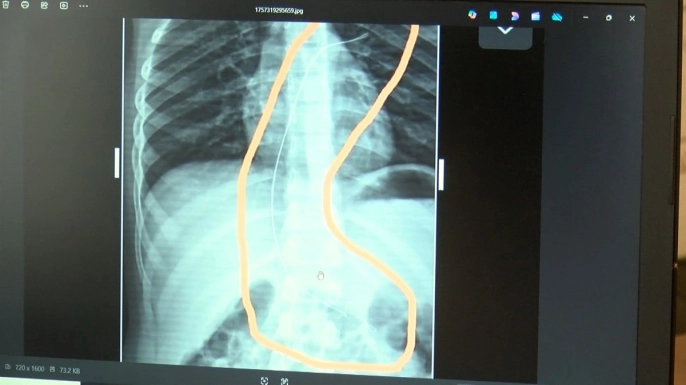

Hastanede çekilen röntgen ve MR görüntülerinde, Aram'ın vücudunda 18 santimetre uzunluğunda bir kateterin bulunduğu görüldü. Diyarbakır'daki Gazi Yaşargil Eğitim ve Araştırma Hastanesi Kadın Doğum ve Çocuk Ek Binası'na sevk edilen Aram, 5,5 saatlik riskli bir ameliyatla bu kateterden kurtarıldı. Ameliyat sonrası yapılan incelemeler, kateterin kalp kapakçığına ve ciğerlerine zarar verdiğini ortaya koydu.